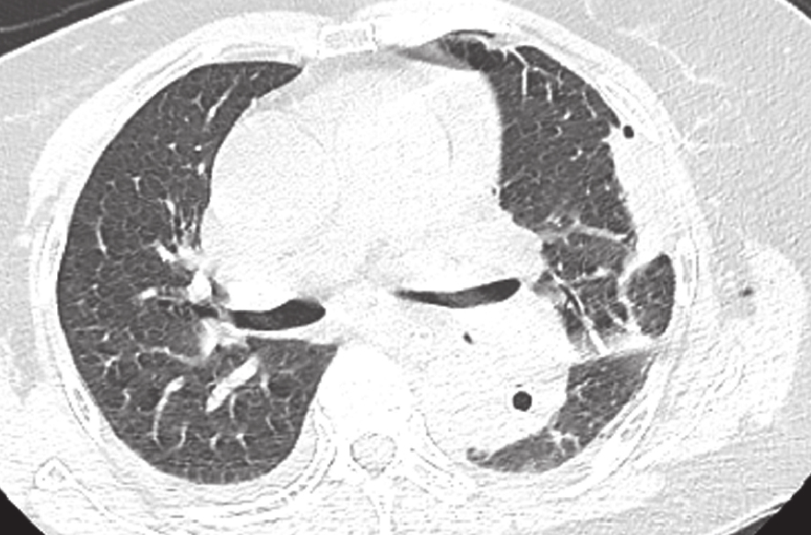

双肺索条灶是指在肺部影像学检查(如X光或CT扫描)中观察到的条索状或线状的高密度阴影。这些阴影通常代表了肺组织的纤维化改变,可能是由慢性肺炎、肺结核等多种原因引起的,具体如下:

4、间质性肺疾病:这类疾病涉及肺泡和肺间质的炎症和纤维化,也会形成索条灶。

对于发现有双肺索条灶的患者,通常需要结合临床症状、病史、实验室检查及可能的组织活检来确定具体的病因。如果患者无明显症状,且索条灶被认为是陈旧性病变,则可能不需要特别治疗,但需要定期随访观察。